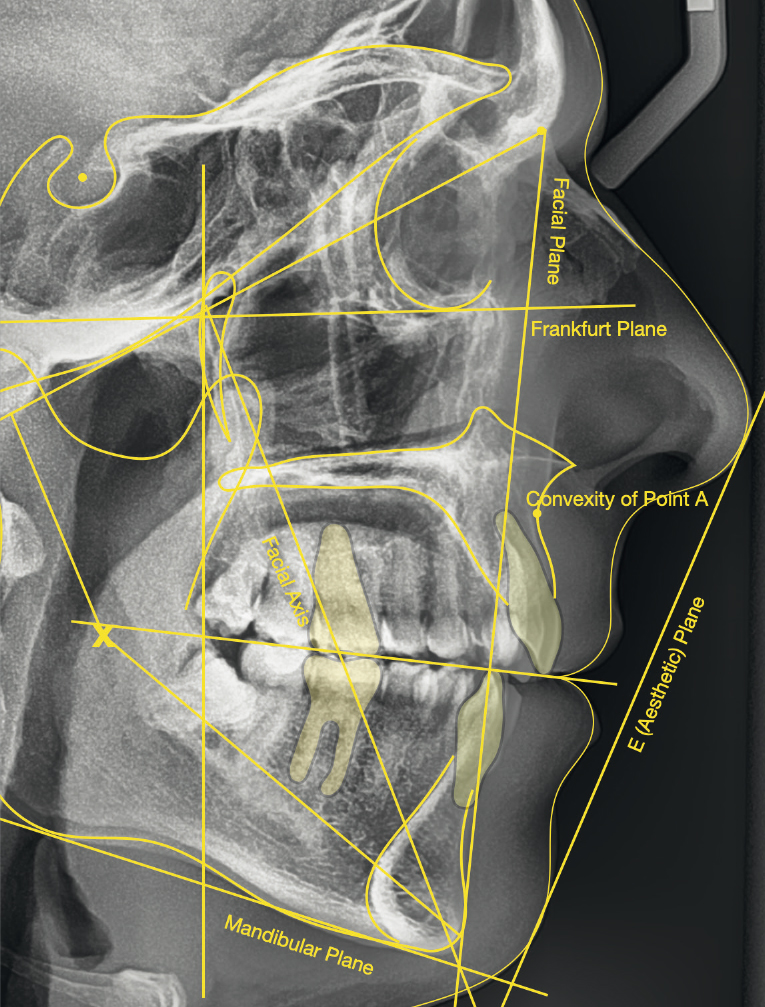

The cephalometric analysis showed a skeletal Class II malocclusion (convexity of Point A: 4.9 mm), a slightly retruded chin position (facial depth: 78.1°) and a skeletal open bite tendency (lower facial height: 53.19°; facial axis: 80.58°; Fig. 9). The mandibular incisors were lingually tipped (Li–APog: 9.3°) and retruded (Li–APog: 1.55 mm), and there was an increased inter-incisal angle of 142.9°.

Treatment results

The post-treatment extra-oral photographs showed the improvement of the smile aesthetics (Figs. 51–58). A solid bilateral Class I occlusion was achieved with normal overjet and overbite. The dental arches were well aligned and levelled, and even the severe rotation of the mandibular left second premolar was corrected with aligners only. The post-treatment cephalometric evaluation (Fig. 59) showed an improvement in the anteroposterior position of the mandibular incisors (Li–APog: 2.21 mm) while maintaining the facial height (lower facial height: 53.12°; facial axis: 83.96°; Table 1).

Deviation analysis using optical metrology

A deviation analysis between the final clinical result and the initial situation was conducted to ascertain the extent of vertical movement in the posterior segments (Fig. 61). This was done to confirm the hypothesis that the relatively thick aligners would assist in bite closure by helping to intrude the posterior segments. The software used for this analysis was GOM Inspect Pro (Carl Zeiss GOM Metrology), which uses a highly accurate method of using optical metrology to measure deviations between two 3D data sets. The results confirmed intrusive movement of the molars and premolars, especially on the right side. The aggregate vertical intrusive movement was in the range of 0.5–1.0 mm. Conventional cephalometric tracings are unable to recognise movements of this order (Fig. 59).

Fig. 59: Post-treatment lateral radiograph with cephalometric tracing.